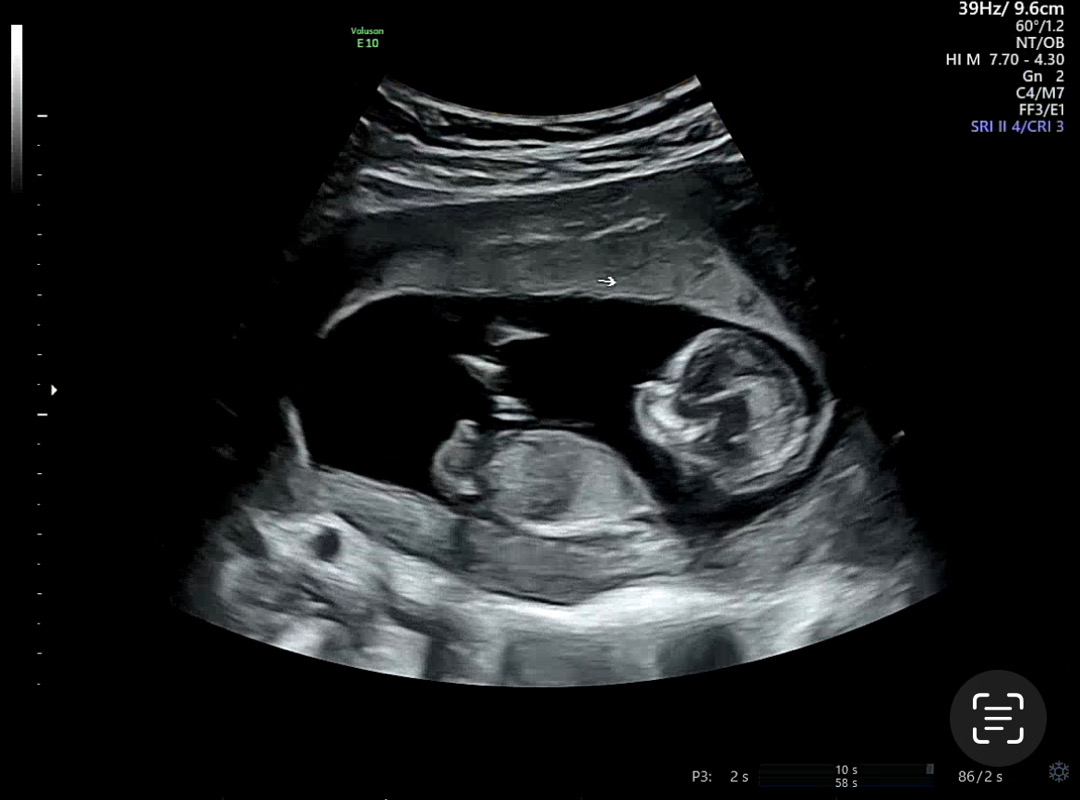

12주3일 차 사진이구요 봐도 잘 모르겠어서 여쭤봅니다 ㅎㅎ 아들일까요? 딸일까요?

각도법 한번 봐주세용~!